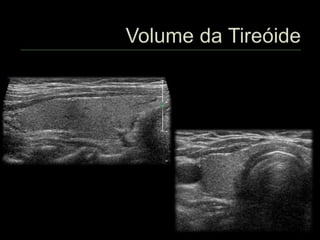

 Volume do lobo = D1 x D2 x D3 x 0,523

 Volume do ístmo = D1 x D2 x D3 x 0,523

 Volume da tireóide = vol. lobo direito + vol. lobo esquerdo + vol. istmo

 Há autores que utilizam a constante : 0,479 (OMS).

 Istmo < 3 mm de espessura

 Volume praticamente desprezível

 Istmo entre 3 e 6 mm de espessura

 Volume próximo a 1,0 cm³

 Istmo ≥ 6 mm de espessura

 Calcular o volume

 Adultos

 Volume: 6 – 15 cm³

 Variações

 Idade

 Sexo

 Superfície corpórea

 Ingestão de iodo

 Fatores genéticos